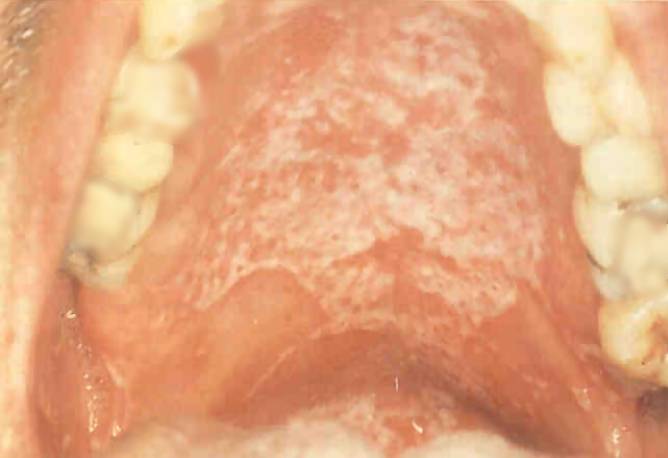

Oральный кандидоз

На небе пациента (вверху) и на языке (внизу) присутствуют симптомы орального кандидоза, оппуртинистическая грибковая инфекция